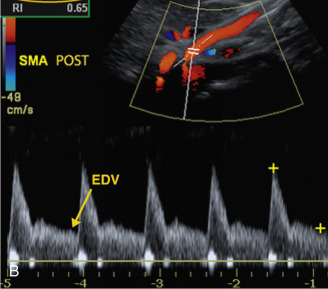

A) Las ondas Doppler espectrales de la arteria mesentérica superior (AMS ) en ayunas muestran un patrón de flujo de alta resistencia

(B) La imagen Doppler espectral de la AMS en estado posprandial de este paciente muestra un aumento en el intervalo de la velocidad sistólica máxima (VSM ) y la VTD. Obsérvese el aumento de la VTD a 55 cm/s.